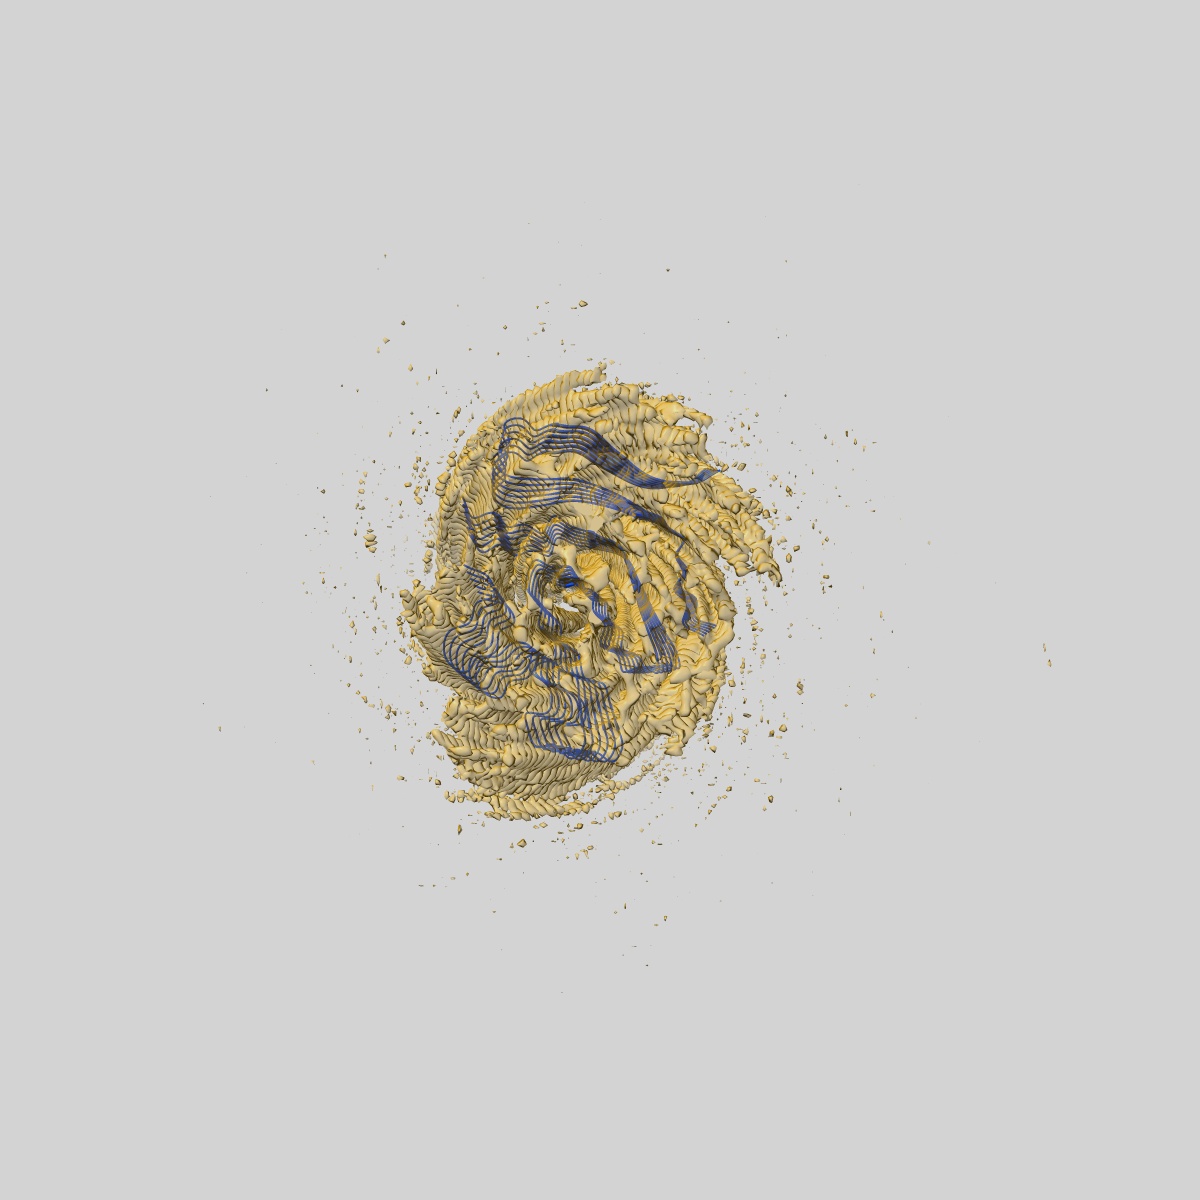

Structure of heteromeric amyloid filament of TDP-43 and AXNA11 from FTLD-TDP Type C (variant 2)

Helical reconstruction2.9 Å

Sample: heteromeric amyloid filament of TDP-43 and AXNA11 from FTLD-TDP Type C (variant 1)

Heteromeric amyloid filaments of ANXA11 and TDP-43 in FTLD-TDP Type C.

- Arseni D, Nonaka T, Jacobsen MH, Murzin AG, Cracco L, Peak-Chew SY, Garringer HJ, Kawakami I, Suzuki H, Onaya M, Saito Y, Murayama S, Geula C, Vidal R, Newell KL, Mesulam M, Ghetti B, Hasegawa M & Ryskeldi-Falcon B. (2024) Heteromeric amyloid filaments of ANXA11 and TDP-43 in FTLD-TDP Type C. Nature,